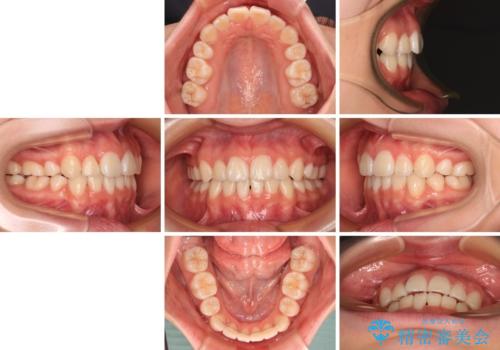

前歯のデコボコとクロスバイトを治したい ワイヤー装置による抜歯矯正

上下の骨格での左右差が小さかったことと、抜歯矯正であったことで、上下正中の位置をきれいに合わせることができました。